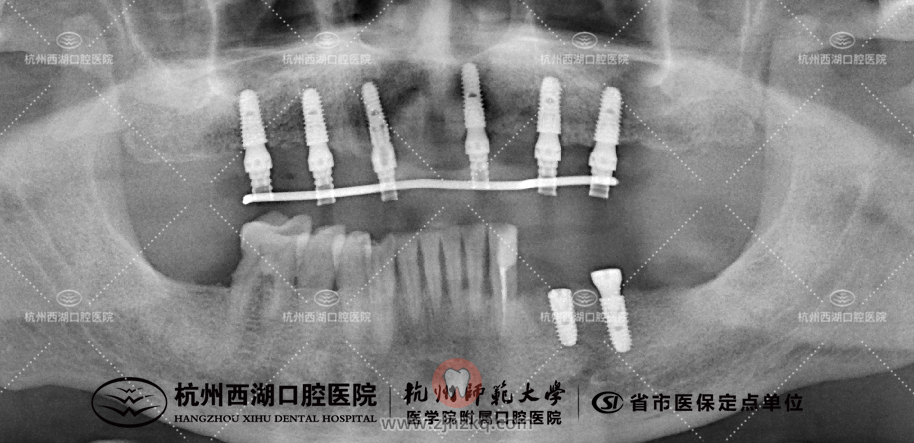

种植团队采用All-on-6即刻修复技术,为孔叔叔上颌植入6颗种植体,即日戴牙完成半口修复。

术后CBCT照如下